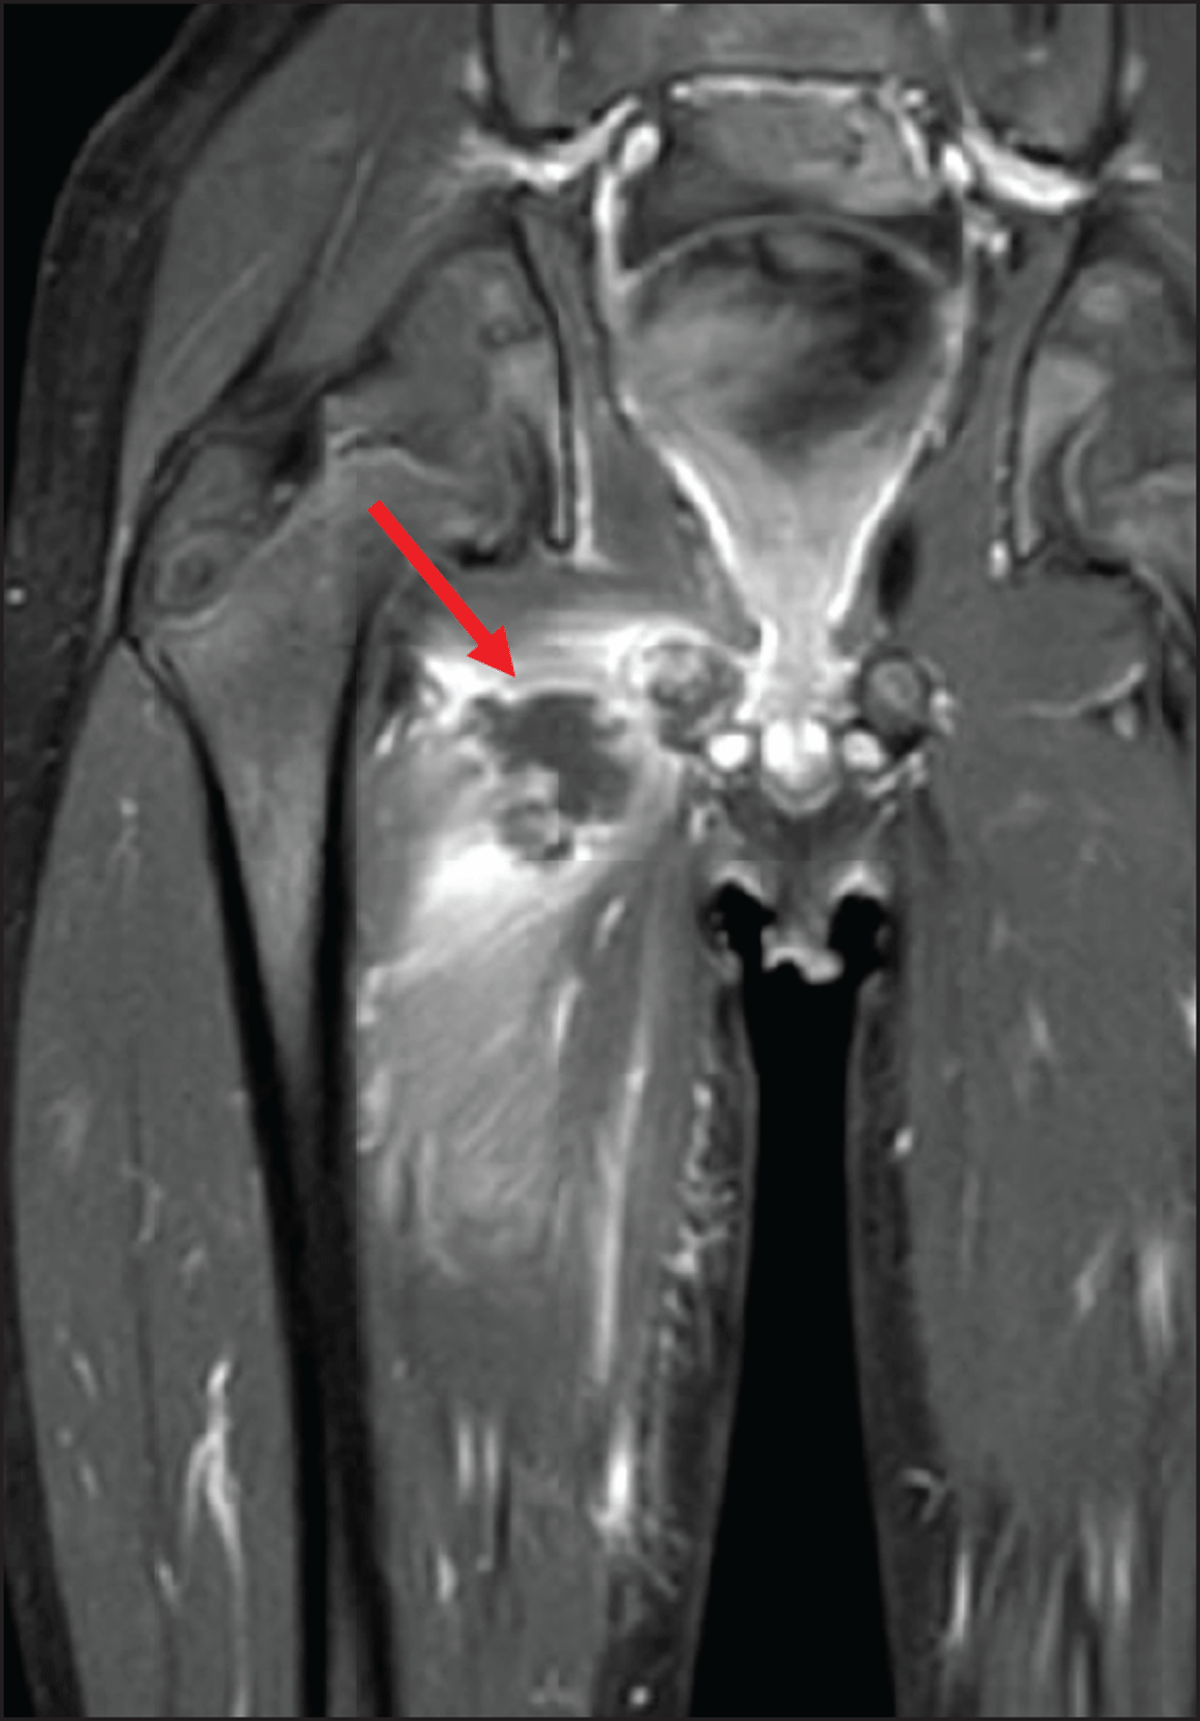

At this time, the blood analysis showed high white blood cells (18.500/mm3) and CRP (171.6 mg/L). Magnetic resonance imaging (MRI) (Figures 1, 2, 3) revealed a 3 cm long subperiosteal collection in contact with the right ischiopubic synchondrosis (arrowheads), suggestive of an abscess (arrows on axial. Figure 1, and coronal, Figure 2, post-contrast fat-saturated T1-weighted images). The abscess extended to the proximal part of adductors compartment and the right ischiopubic branch was involved by edema, appearing as high signal on short-tau inversion-recovery (STIR) imaging (Figure 3). Extensive edema was also visible in the surrounding tissues.

Figure 2